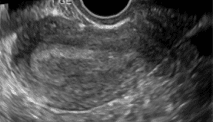

Sandsynlig intrauterin graviditet

Intrauterin echogen sæk‑lignende struktur. På dansk: Fund i livmoderen som kan være graviditet men ikke helt sikkert.

Gestationssæk

Ekkotom, sfærisk struktur omgivet af tyk hyperekkoisk dobbelt ring repræsenterende decidua. Ligger ofte excentrisk i forhold til midtlinien.

Gestationssækken måles ved gennemsnit af minimum 2 diametre af det ekkotomme område vinkelret på hinanden, optimalt medtages diameteren i tværplanet vinkelret herpå.